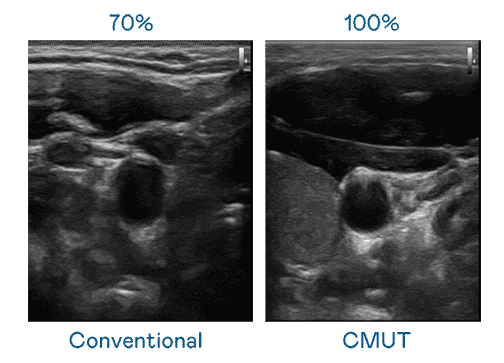

CMUT 技术是一种用电容式微机电元件来产生超音波讯号的技术。。。与传统 PZT 压电式技术相比,,,CMUT 频宽增加 30%,,更宽频的超音波讯号让影像解析度大幅提升,,,,是实现高影像品质医疗超音波扫描、、、促进精准医疗发展的关键技术。。。

超音波影像的解析度高低,,,,首先取决于探头能发出的讯号频宽。。。。赏金国际 CMUT 可提供高清晰的超音波讯号,,提供高频宽、、高灵敏度、、、影像纹理细节更高的超音波影像,,,协助医护人员缩短影像判读时间及利用精准的医疗影像进行诊断。。